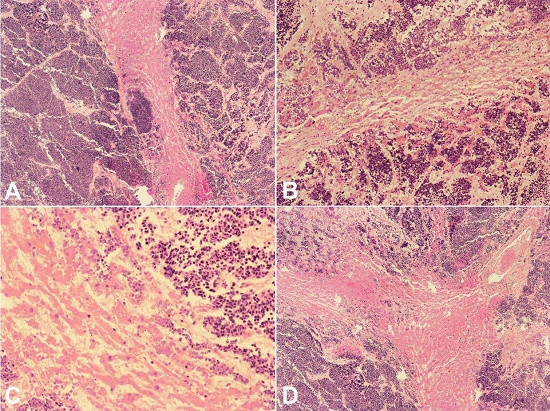

The pulmonary lesion (Figure 3) was an undifferentiated lymphocytic-like neoplasm, mainly of small cells, with nuclear characteristics (salt and pepper chromatin), which allowed the diagnosis of small cell carcinoma. The immunohistochemical findings confirmed a small cell carcinoma; in fact, these tumor cells were strongly and diffusely positive for cytokeratin cocktail MNF116, CD56, and TTF-1, and faintly positive for synaptophysin and chromogranin A.

The liver was enlarged due to massive SLCL infiltration, which was also responsible by the cholestasis (Figures 4 and 5).